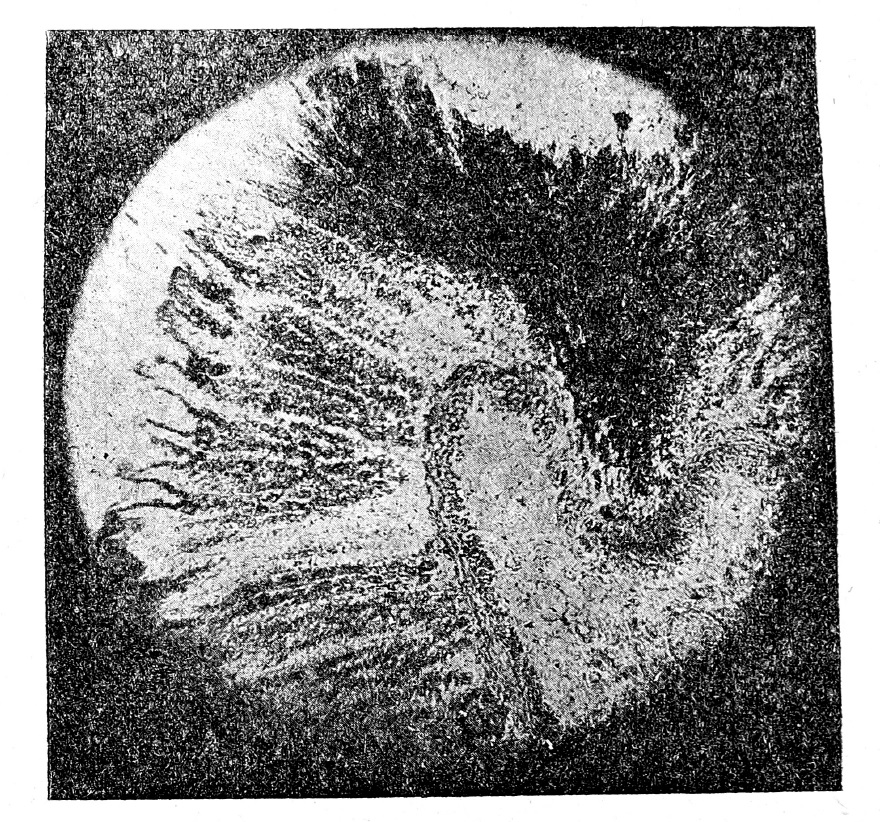

Рис. 1. Слизистая оболочка желудка кролика при бе шенстве. Глубокий инфаркт через всю толщу слизи стой оболочки (справа).

В глубину слизистой оболочки инфаркт вдается в виде клина, усеченного конуса, над субмукозой его окружность значительно меньше в сравнении с размерами на ‘Свободной поверхности слизистой оболочки. Ось инфаркта наклонена в соответствии с ходом вступающих в слизистую оболочку сосудов. В свежем виде инфаркт темно-красного цвета, который затем переходит в черно-красный цвет. Инфаркты неравномерно рассеяны по слизистой оболочке желудка, весьма редко встречаются в числе 1—2, чаще в числе 3 — 5 и обыкновенно до 5—10, а иногда в громад ном числе до 20—85 (в од ном случае бешенства у со баки).

На месте инфаркта подслизистая оболочка собрана в складку—выступ вследствие сокращения мышечной ткани. Складка имеет форму более или менее высокой и широкой кишечной ворсинки, иногда с довольно сильным перехватом у основания. Свод ворсинки в виде полукруга или с вторичным, подчас довольно глубоким, втягиванием. Инфаркт обыкновенно расположен в виде клина в толще слизистой оболочки на вершине складки и реже спускается на ее боковые поверхности. Широкой стороной—основанием—клин обращен к поверхности слизистой оболочки, а вершиной к подслизистой. Встречаются поверхностные инфаркты, которые захватывают только ⅓ или 2/з толщи слизистой оболочки, но сравнительно чаще клином инфаркта занята вся толща слизистой оболочки.

На месте инфаркта обнаруживается геморрагическая инфильтрация слизистой оболочки желудка. Сосуды, особенно вены и капилляры, растянуты, запружены форменными элементами крови Париваскулярные и тканевые пространства более или менее сильно растянуты и также забиты эритроцитами и отдельными лейкоцитами. Железы раздвинуты геморрагическим инфильтратом; эритроциты видны также в просвете же лез и на поверхности слизистой оболочки. Ткань инфаркта вначале вполне сохраняет рисунок и окраску. В дальнейшем замечается ослабление окраски и постепенно выступают все признаки некроза и распада инфильтрата и ткани инфаркта, как покровного и железистого эпителия, так и соединительно-тканной основы, и сглаживание рисунка. Эритроциты обесцвечиваются, теряют контуры, сливаются в однородную массу с вы падением и отложением пигмента. Эпителиальные клетки выступают в виде лишенных ядер, обесцвеченных глыбок, которые затем распадаются в бесформенную зернистую массу. Соединительно-тканная основа окрашивается базофильно и, наконец, теряет волокнистость и способность окрашиваться. Границы инфаркта резкие или геморрагическая инфильтрация выражена в более слабой степени, сглаживая за пределами инфаркта его границы.